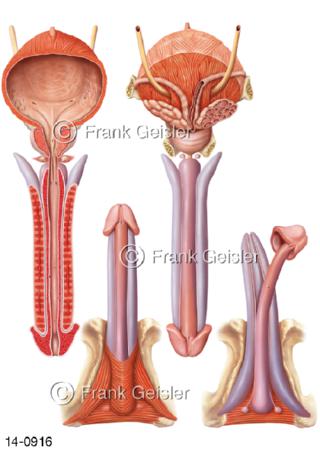

Bildergalerie Urogenitalsystem

Bilder zum Urogenitalsystem mit Urogenitalorgane, Urogenitaltrakt, zum Harn- und Geschlechtsapparat, Harnorgane und Geschlechtsorgane, Organe der Harnwege und der Fortpflanzung, Harnorgane und Geschlechtsorgane im männlichen und weiblichen Urogenitalsystem